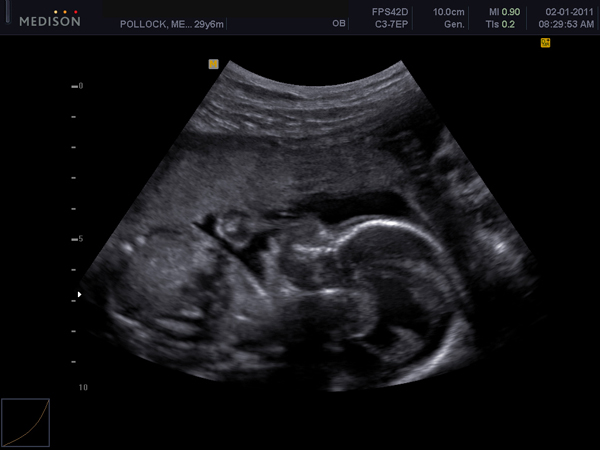

This month marks our 2-year spina bifida birthday. Getting that diagnosis during our 20-week prenatal visit was the most scary, overwhelming, uncertain, difficult moment I’ve faced so far in our lives.

We were just supposed to get a peak at our little peanut. Peanut’s gender wasn’t a big deal for us to find out ahead of time. We were looking forward to the surprise at birth.

Unfortunately that book didn’t make it long around our house. It made me feel like an outsider hoping that one day during our ultrasound Dr. Stewart would say, “Wait a minute. Peanut’s back is closed and there isn’t any fluid in his ventricles. Looks like we’re going to be waiting to deliver when Peanut wants to be delivered.”